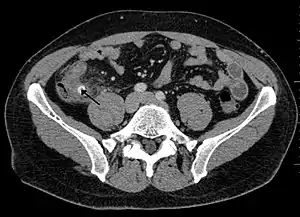

Computed tomography

Where it is readily available, computed tomography (CT) has become frequently used, especially in people whose diagnosis is not obvious on history and physical examination. Although some concerns about interpretation are identified, a 2019 Cochrane review found that sensitivity and specificity of CT for the diagnosis of acute appendicitis in adults was high.[50] Concerns about radiation tend to limit use of CT in pregnant women and children, especially with the increasingly widespread usage of MRI.[51][52]

The accurate diagnosis of appendicitis is multi-tiered, with the size of the appendix having the strongest positive predictive value, while indirect features can either increase or decrease sensitivity and specificity. A size of over 6 mm is both 95% sensitive and specific for appendicitis.[53]

However, because the appendix can be filled with fecal material, causing intraluminal distention, this criterion has shown limited utility in more recent meta-analyses.[54] This is as opposed to ultrasound, in which the wall of the appendix can be more easily distinguished from intraluminal feces. In such scenarios, ancillary features such as increased wall enhancement as compared to adjacent bowel and inflammation of the surrounding fat, or fat stranding, can be supportive of the diagnosis. However, their absence does not preclude it. In severe cases with perforation, an adjacent phlegmon or abscess can be seen. Dense fluid layering in the pelvis can also result, related to either pus or enteric spillage. When patients are thin or younger, the relative absence of fat can make the appendix and surrounding fat stranding difficult to see.[54]